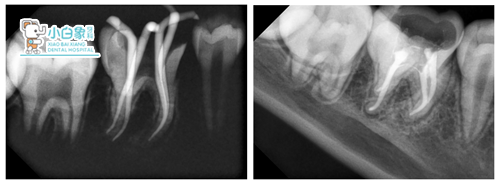

治疗过程:36必兰麻下去腐质,揭髓顶,拔髓4根,远中颊舌侧18mm,近中颊舌侧19mm,M3预备,冲洗,隔湿干燥,根管内牙胶尖+根管糊剂充填,树脂垫底。